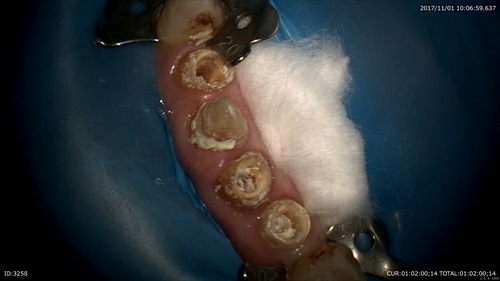

午前中のマイクロエンドケース

大切な前歯の根の先に膿が溜まってしまっています。

ラバーダムをかけ

ガッタパーチャを取ると膿があがってきました。

マイクロスコープで根尖まで見えます。

見えれば感染がとれます。